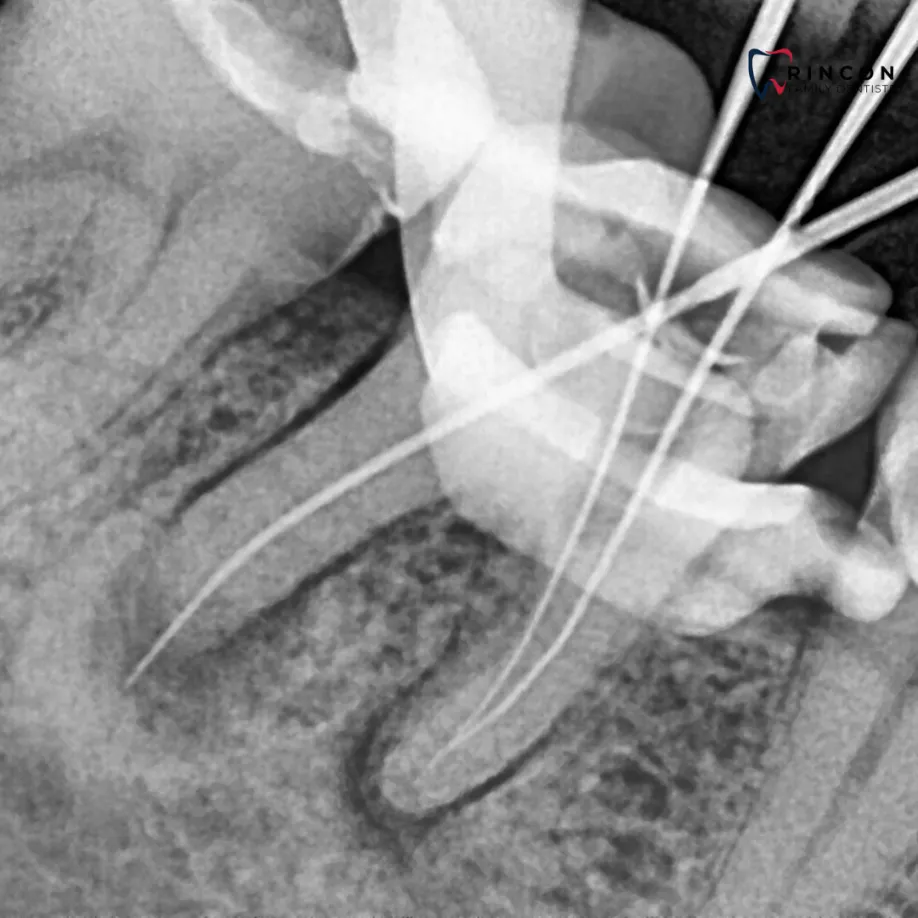

Periapical X-rays

If sharp pain or swelling appears near a specific tooth, a periapical scan helps identify decay, infection, or bone loss. It captures the full tooth from crown to root, offering a complete picture of its condition. Our advanced digital sensors deliver crisp results in seconds while keeping exposure low.